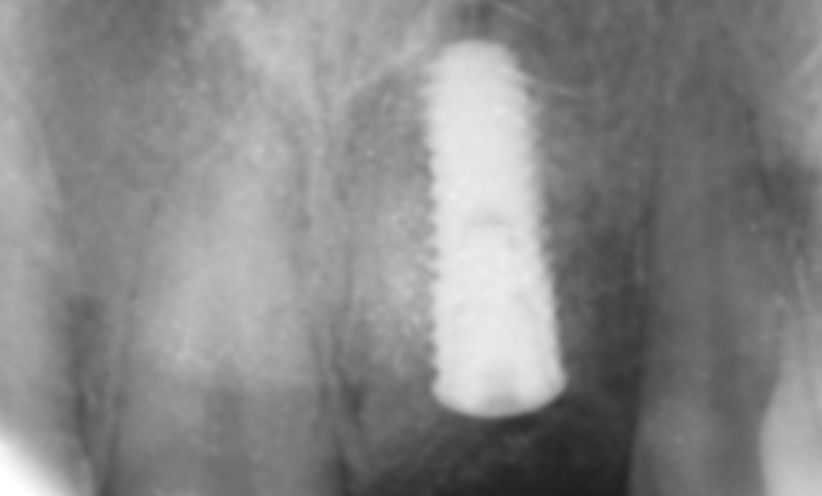

Case 17